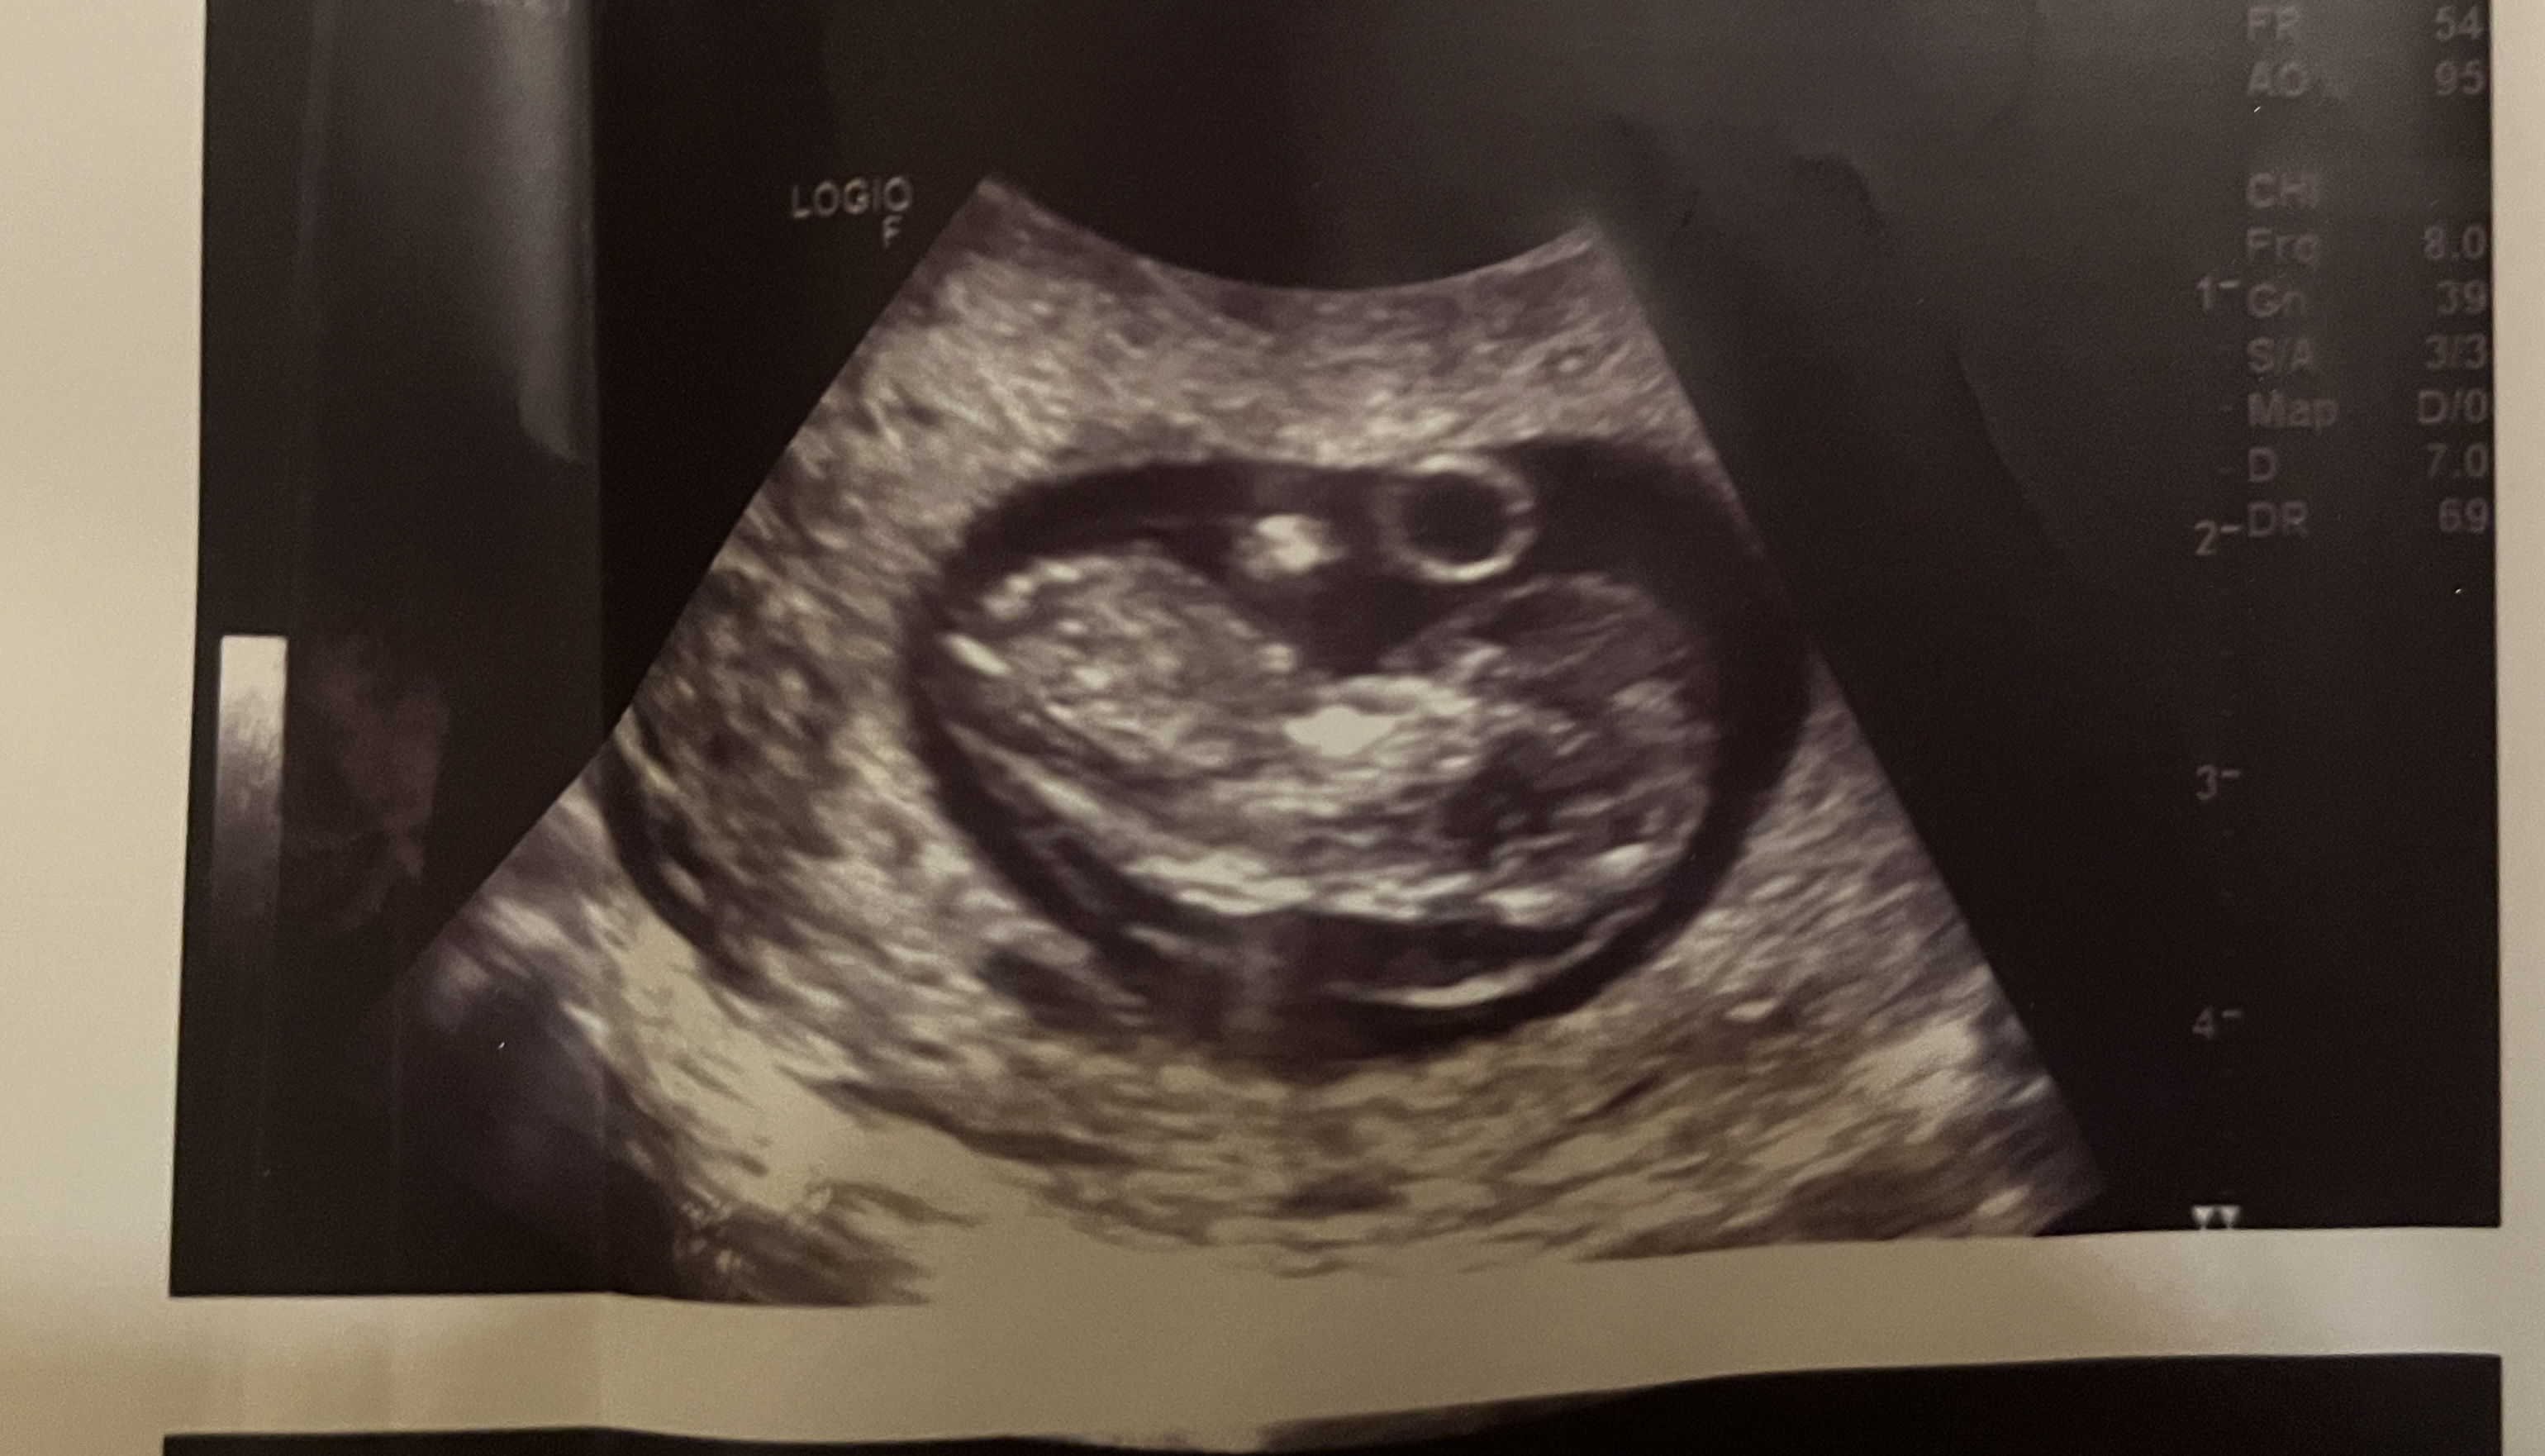

Witam! Mam podobny problem. Byłam na USG w poniedziałek i zdjęcie USG bardzo podobne. Podsyłam w załączniku. W poniedziałek idę na test Nifty, a za tydzień na badania prenatalne na NFZ. Czy możesz powiedzieć co okazało się przyczyna? Mam podobne odczucie - naczytałam się za dużo na temat obrzęku i bardzo się boję. Choć Twoja wiadomość bardzo mnie uskrzydliła! PozdrawiamJa w pierwszej ciąży w 10 tc na badaniu w luxmedzie też usłyszałam, że jest obrzęk - no i lekarka się mnie pytała, czy byłam chora/miałam jakieś infekcje. Akurat byłam zdrowa, więc przez 2 kolejne dni jak się naczytałam o obrzęku płodu to wiadomo, nie było za ciekawieJeszcze wyjeżdżałam na 2 tyg za granicę na urlop i nie miałam jak zrobić USG np za tydzień. Kolejnego dnia byłam na jeszcze jednym USG i ten obrzęk też był widoczny. Na dzień przed wyjazdem zrobiłam Nifty, wyniki przyszły pod koniec urlopu, że jest wszystko ok

Ale i tak na prenatalne szłam pełna strachu - jak się okazało niepotrzebnie, wszystko było super i w te 2,5 tygodnia obrzęk kompletnie zniknął. Co się napłakałam i namartwilam przez ten czas to moje. Mam nadzieję, że u ciebie historia też się dobrze skończy

Nie znalazłam przyczyny - robiłam badanie na toxo, parwowirus19 i cmv i wyniki były ok. USG z obrzękiem miałam robione chyba koło 9+6 a kolejne dopiero po 3 tygodniach, bo wyjeżdżałam za granicę. I w tym czasie obrzęk zniknął. Na pewno trochę uspokoiły mnie wyniki Nifty, które przyszły w międzyczasie. Trzymam kciuki, aby u Ciebie też wszystko dobrze się skończyłoWitam! Mam podobny problem. Byłam na USG w poniedziałek i zdjęcie USG bardzo podobne. Podsyłam w załączniku. W poniedziałek idę na test Nifty, a za tydzień na badania prenatalne na NFZ. Czy możesz powiedzieć co okazało się przyczyna? Mam podobne odczucie - naczytałam się za dużo na temat obrzęku i bardzo się boję. Choć Twoja wiadomość bardzo mnie uskrzydliła! Pozdrawiam![]()